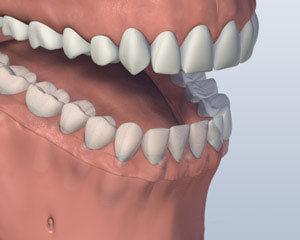

虽然很多患者都没有戴上假牙的问题, 有些人觉得很难穿,用较低的假牙吃. 一些 种植体支持的替代选项 可如果你缺少你所有的下牙.

您是否丢失了所有你的下牙?

1. 之前

2. 植入放置

3. 义齿附